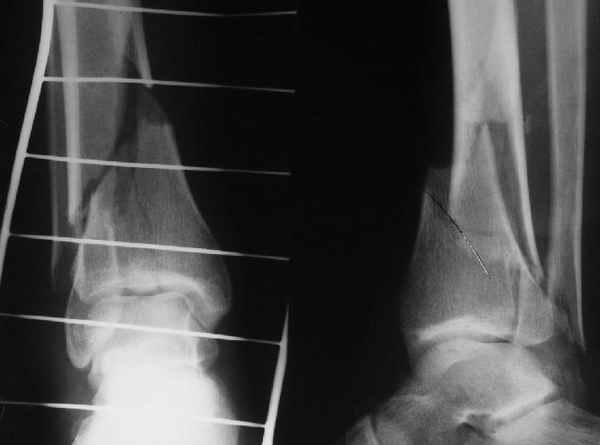

A propos fibular fixation if one is eager to stabilize it separately. In the fracture pattern a way of closed fixation by V-shaped stressed wire (advanced by colleagues from Moscow, prof. Lazarev A.F. et al.) must be excellent. We use indirect closed reduction by the external fixator. Example attached, that fibular fracture is even more suitable for plating but the wire did the job.

Еще, кстати, о фиксации лодыжки, если уж непременно хочется ее отдельно стабилизировать - при таком характере перелома замечательно должен сработать предложенный проф. Лазаревым с соратниками способ фиксации напряженной V-образной спицей. Опять же, открытая репозиция не нужна, мы делаем непрямую репозицию именно аппаратом. В приложении пример, там перелом малоберцовой куда менее поперечный, чем в данном случае, но все равно получилось закрыто без пластинки.